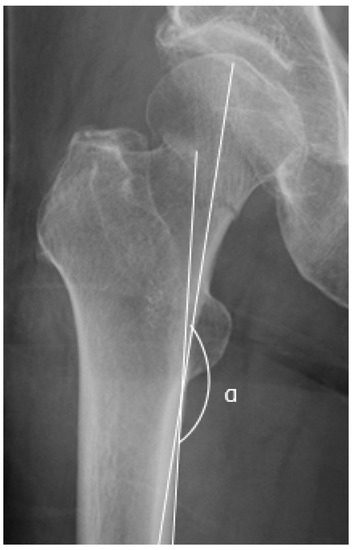

2.5. Garden Alignment Index